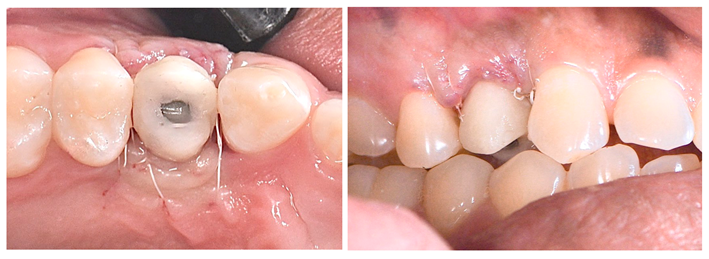

Constatada a perfeita osteointegração, realizou-se a reabertura do implante e instalação do dente provisório (Figuras 12 e 13) visando o condicionamento gengival para formação e maturação correta do perfil gengival previamente à confecção da coroa definitiva.

O presente caso clínico mostra que essas abordagens combinadas – extração atraumática, implante imediato, enxerto e preservação alveolar – desempenham um papel fundamental na reabilitação oral, permitindo a substituição de dentes perdidos por implantes dentários com resultados estéticos e funcionais bastante satisfatórios e previsíveis.